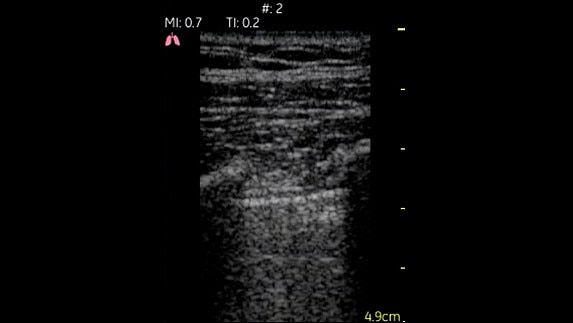

Akciğerler